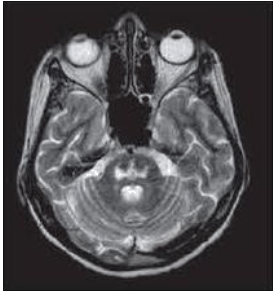

Paciente, 56 anos, internada em leito de UTI devido a complicações da Covid-19, evoluindo com várias intercorrências ao longo dos seus 24 dias de internação hospitalar, como diversos distúrbios hidroeletrolíticos, com necessidade de correção. A paciente evoluiu com tetraparesia espástica e realizou o seguinte exame de imagem:

Assinale o provável diagnóstico da paciente.